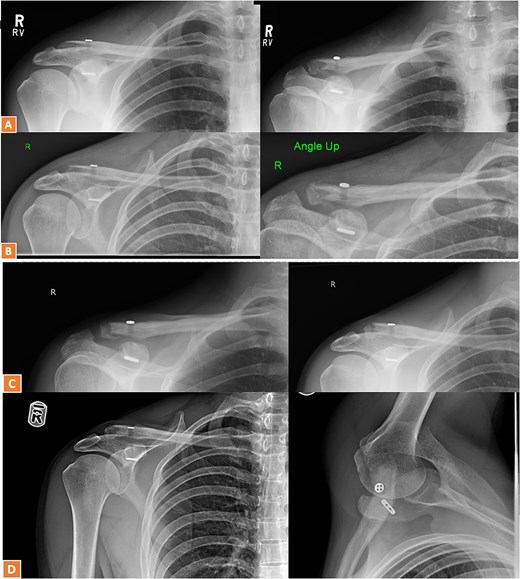

A 30-year-old male presented with an unstable lateral clavicle fracture and skin tenting after a rugby injury. Imaging revealed a Neer type IV equivalent fracture (Fig. 3). He underwent open reduction and internal fixation with coracoid exposure and TightRope placement, reinforced with fiber-wire. Postoperative recovery included sling immobilization followed by pendular exercises. Despite delayed radiological union, he achieved full range of motion and strength by three months, with only mild, asymptomatic clavicular prominence. He returned to physically demanding work without restrictions, and final imaging confirmed union (Fig. 4A–C).

Radiographs of second case showing a displaced lateral end clavicle fracture with deformity and dorsal displacement.

(A–C) Radiographs showing complete healing of the second case and union at 3, 6, and 12 months post-operatively.